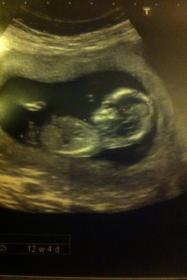

baby is 12 wks 4 days here. I would really like your opinion please!! I have already posted on another forum and would like to see if you lovely ladies think the same!

Attachment 1034Attachment 1035

I HAVE POSTED THE PICS AGAIN. PLEASE SCROLL DOWN X